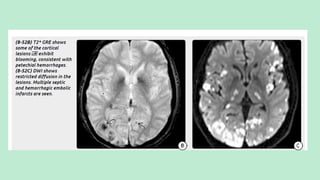

MRI: Multifocal peripheralT2/FLAIR hyperintensities. Hemorrhagic emboli

cause "blooming" onT2* sequences (most sensitive sequence: DWI).

Typical finding in multiple emboli infarcts: Small peripheral foci of

diffusion restriction in several different vascular distributions.

T1 C+ imaging may show multiple punctate enhancing foci.

Septic emboli often demonstrate ring enhancement, resembling